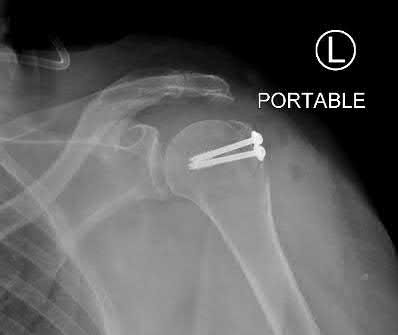

Question 12:

A 55-year-old patient presents with a slowly enlarging, painful mass in the proximal humerus. Biopsy reveals a hyaline cartilage matrix with cellular atypia, confirming a diagnosis of central conventional chondrosarcoma. Which of the following genetic mutations is most frequently identified in this specific tumor?

Correct Answer: IDH1 / IDH2

Explanation:

Mutations in the isocitrate dehydrogenase genes, IDH1 and IDH2, are found in up to 50-60% of central conventional chondrosarcomas and enchondromas. EXT1 and EXT2 mutations are characteristic of multiple hereditary exostoses (osteochondromas). GNAS mutations are seen in fibrous dysplasia. TP53 and RB1 mutations are hallmark aberrations in osteosarcoma.